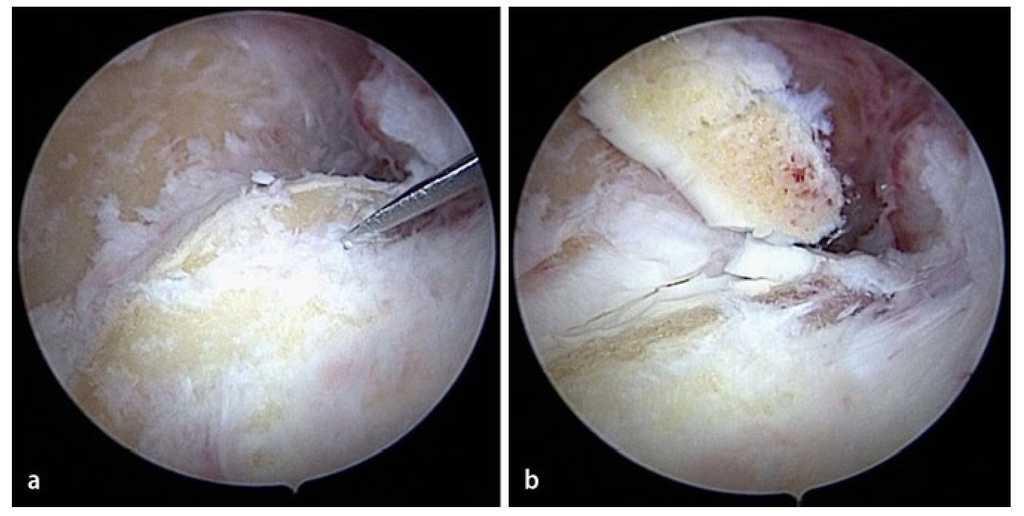

Fig. 10 Después de la sinovialectomía se extraen los cuerpos articulares libres. Según el tamaño de estos cuerpos, la extracción se realizará mediante pinzas o un resector sinovial.

Fig. 11 a, b) Los osteofitos en la zona del proceso coronario se extraen con un cincel Lambotte. c) Los fragmentos osteocondriales se extraen de la articulación con una pinza de agarre. d) El proceso coronoides remanente se alisa con el resector sinovial o una fresa de bola (no representado en la imagen).

Fig. 12 Las formaciones osteofíticas del borde del húmero anterior se pueden extraer progresivamente con una fresa de bola.